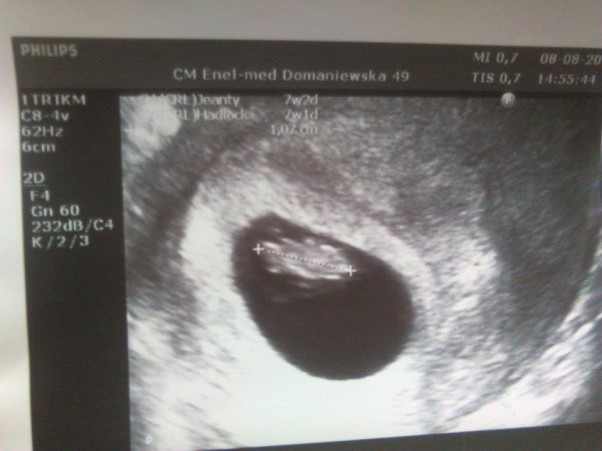

Za nami pierwsze usg i nasze szczęście z bijącym serduszkiem na monitorze. Kocham całe 1,07 cm ;-)